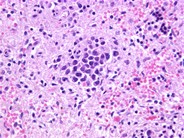

Lymphoma cells present within the subendothelium and subendothelial capillaries of a large pulmonary vein. The patient was a 72-year-old woman who presented with multiple strokes of unclear etiology. Ultimately a brain biopsy revealed the diagnosis. She subsequently became increasingly tachypneic and developed multi-lobar pneumonia. The presence of lymphoma cells within the alveolar capillaries, interrupting gas exchange, can explain the patient's respiratory symptoms.